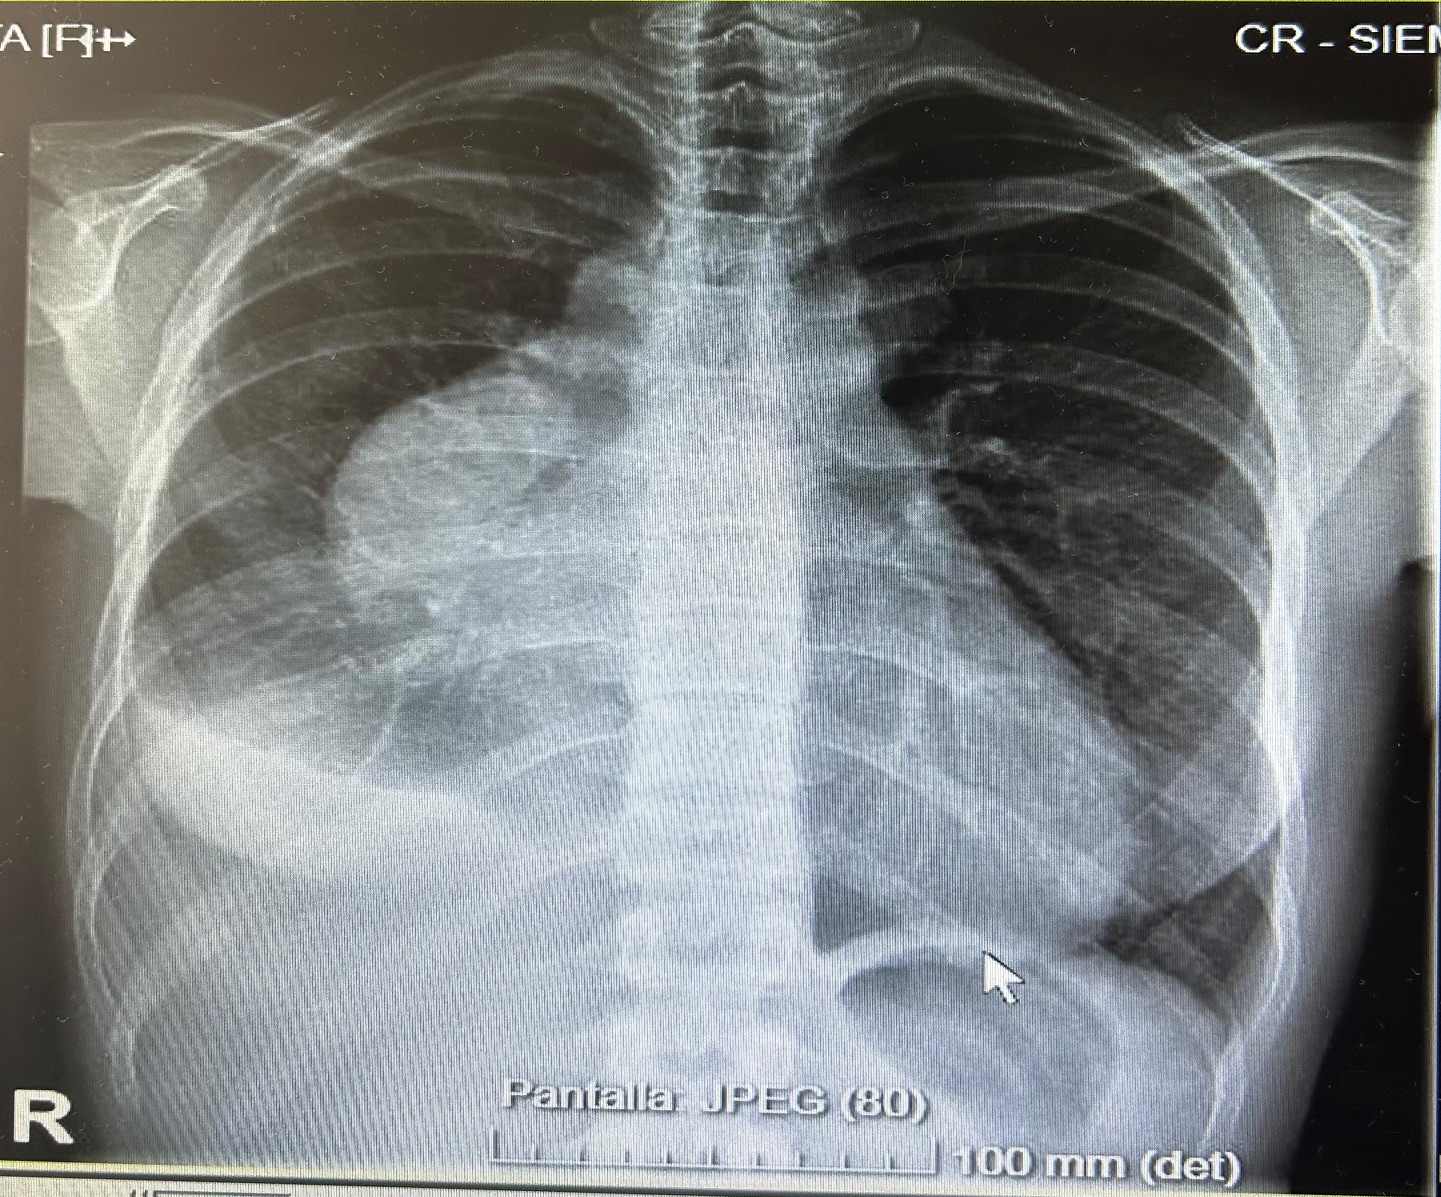

Radiografía de tórax: derrame pleural derecho, ocupación en mediastino anterior. No se observan infiltrados claros.

La ecografía clínica desempeñó un papel fundamental en la evaluación inicial del paciente, permitiendo una detección rápida y precisa de hallazgos que guiaron la toma de decisiones clínicas. La ecocardioscopia realizada reveló un derrame pericárdico moderado, sin signos de taponamiento cardíaco y un derrame pleural derecho significativo. Estos hallazgos fueron esenciales para descartar la presencia de un cuadro obstructivo que pudiera haber requerido una intervención inmediata. Además, la ecografía permitió valorar el estado hemodinámico de la paciente de forma no invasiva, asegurando que el derrame pericárdico no comprometiera la función cardíaca. En la radiografía de tórax se objetiva una masa mediastínica. La capacidad de detectar y cuantificar de forma precisa tanto el derrame pleural como el pericárdico sin necesidad de esperar a pruebas más complejas, permitió que la paciente fuera ingresada de manera adecuada para un estudio exhaustivo y sin demoras innecesarias.